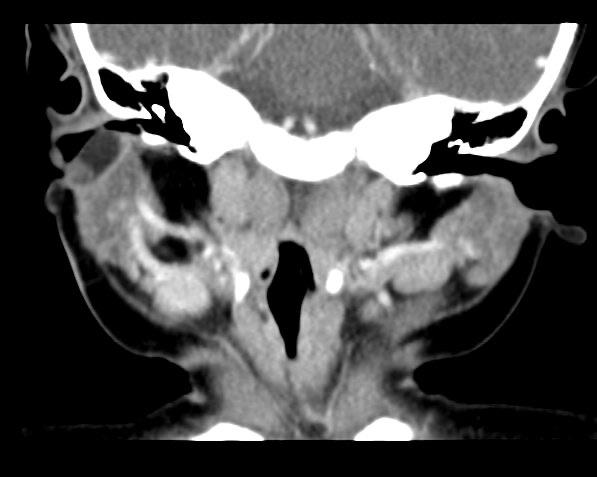

CT表现为病灶位于Pochet’s三角区,常位于舌骨水平以上,最常见于耳周及颌下区。耳周和腮腺内囊状、分叶状、管状低密度影,与耳道关系密切,增强扫描见囊壁或管壁明显强化,部分见管腔与皮肤相通,位于腮腺浅叶或深叶。CT显示病变与面神经、腮腺、外耳道关系密切且复杂多变(图2B),可协助临床医生设计切口,在完整摘除病变的基础上,避免面瘫、外耳道狭窄等。

CT显示右侧腮腺外皮下见一条管状低密度影,大小约0.6*0.6*0.9cm,延续至外耳道。